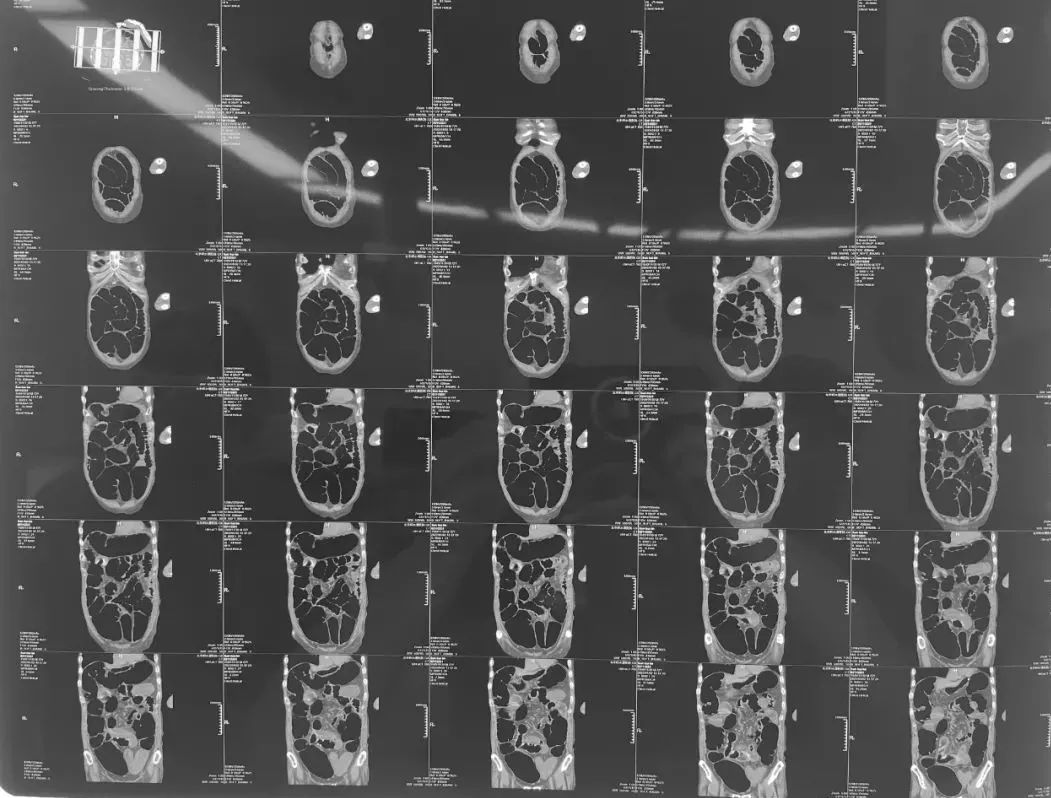

在回龙观院区急诊,一位老年女性患者因严重腹胀就诊,常规完成化验及CT检查后,明确诊断为“急性肠梗阻”。刘亚奇主治医师阅片后快速做出决定,患者需住院急诊手术治疗,因为这种低位的肠梗阻,非手术治疗效果通常不理想,如果不及时处理,肠管扩张水肿进一步严重后,往往会错过手术最佳时机。通过与家属充分沟通病情后,完成防疫筛查和术前准备,于当日傍晚进手术室手术。

二线毕敬涛主任医师会诊后同意手术方案,并亲自主刀,术中探查发现是回盲部结肠肿瘤浸润后腹壁结构,导致完全肠道梗阻,小肠扩张直径超过10cm以上,腹腔空间完全被占据,给手术显露造成了很大困难。手术团队毕敬涛副主任医师和刘亚奇主治医师,在麻醉医生陶岩、杨晓宇以及护士侯丽娜、刘树琪、徐娅敏的密切配合下,克服重重困难,凭借丰富的临床经验和精湛的手术技巧,顺利完成了标准的右半结肠根治性切除术,既解决了肠梗阻问题,又一期完成了肿瘤的根治性切除,避免了患者二次手术,极大的减少了患者痛苦,改善了预后和生活质量。

无独有偶,在刚刚开诊的新龙泽院区急诊,一位老年腹胀患者也在家属的陪伴下前来就诊。老人胀痛难忍,极度虚弱,沟通困难。急诊内科完善检查后,腹部CT提示重度全肠管扩张。急诊外科胡琳医师接诊患者后,详细询问病史查体,仔细分析腹部CT及相关化验结果,同时病房高鹏骥主任医师协助分析病情,综合考虑患者不排除直肠乙状结肠交界肿瘤导致肠梗阻可能,需要急诊手术。患者家属了解病情后,希望节后进行手术治疗,想通过灌肠、胃肠减压方式保守治疗。胡琳医师耐心向患者家属说明错过手术最佳时机将产生的不良后果,患者家属商量后最终决定尽快进行急诊手术。

麻醉医生陈雪、吴泽昊凭借丰富的专业经验,在手术室护士李晶,刘一欣,刘波,刘娟娴熟的护理操作下,手术得以顺利开展。高鹏骥主任医师详细分析患者病情后,在胡琳医师协助下,开腹探查发现病情与术前分析一致,患者直肠乙状结肠交界处有一环状缩窄肿物,考虑肿瘤可能。术中未发现明显腹腔转移,综合根据患者病情,手术行根治性切除直肠肿物,周围淋巴结清扫,远端直肠旷置,近端乙状结肠造瘘。通过高鹏骥主任医师丰富的经验及娴熟的手术技术,手术圆满完成。